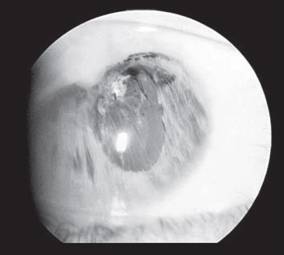

Лазерная корепраксия и фотомидриаз достигается за счет способности ткани радужки сокращаться в направлении лазерного ожога. Для корепрак- сии можно использовать любой коагулирующий лазер, например аргоновый или диодный. Коагуляты диаметром 200-500 мкм наносятся на поверхность радужки, отступя 2-3 мм от края зрачка, в меридиане, в направлении которого требуется подтянуть край зрачка. Мощность излучения подбирается индивидуально, так как она зависит от пигментации, цвета радужки, формы и толщины. В зависимости от сохранившейся площади ткани радужки, формы и положения деформированного зрачка возможно смещение его на 1-4 мм. Наиболее часто корепраксия применяется при смещении зрачка кверху в сторону послеоперационного рубца, образовавшегося при ушивании разрывов и разрезов роговицы, вследствие чего край зрачка прикрывается верхним веком и препятствует нормальной фиксации (рис.

151).

Рис. 151. Корепраксия при смещении зрачка в сторону послеоперационного рубца: а — до операции; б — после лазерной корепраксии аргоновым лазером.